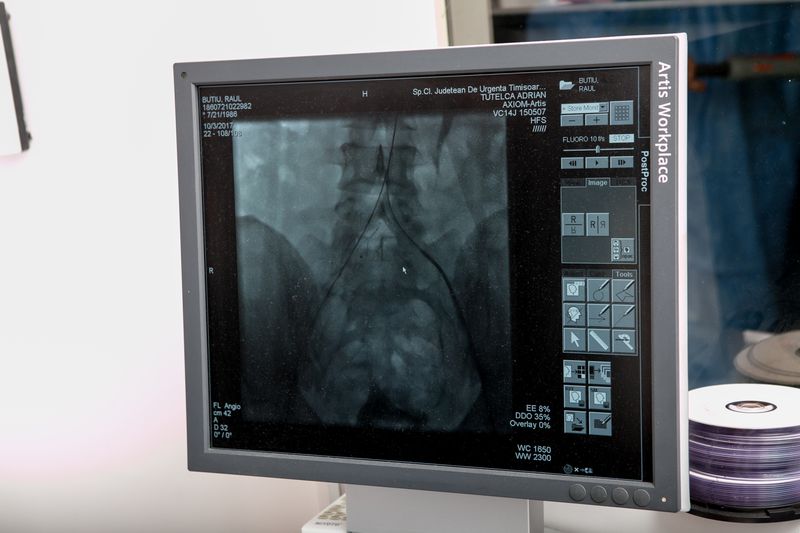

Prima intervenţie a fost făcută la o pacienta de 24 de ani, care a fost diagnosticată cu sindromul May Thurner, care a cauzat o tromboză gravă venoasă.

“Această am tratată împreună cu doctorul Tutelcă cu ceva timp, tot endovascular, trombul respectiv a fost dizolvat, dar a rămas pe loc cauza. Cauza fiind o strâmtoare a unei vene principale a corpului în interiorul abdomenului. Acest sindrom a fost tratat astăzi cu un stent special, este un tratament care este considerat standard în această boală şi avem marea bucurie să-l fi pus împreună pentru prima dată la noi.”, a spus Mihai Ionac, şeful Clinicii de Chirurgie Vasculară.

Cea de-a două premieră se referă la o intervenţie endovasculara la nivelul arterei iliace.Localizarea este deosebit de gravă, ruptură acestui anevrism putând duce chiar şi la deces. Tratamentul s-a realizat prin implantarea pentru prima oară în ţară noastră a unei proteze special construite pentru arteră iliacă.

La cele 2 intervenţii medicii români, Prof. Dr. Mihai Ionac şi Dr. Adrian Tutelcă colaborează cu Dr. Rolf Dammrau, chirurg vascular din Germania, cu experienţă redutabilă în chirurgia endovasculara.

“În medie operaţiile au durat 4 ore. Prima a mers foarte repede, a două a fost un caz mai complicat, cum a spus şi domnul profesor, şi a durat ceva mai mult. Evident că a ieşit totul bine.”, a spus Dr. Adrian Tutelcă, medic specialist radiologie, Spitalul Judeţean Timişoara.